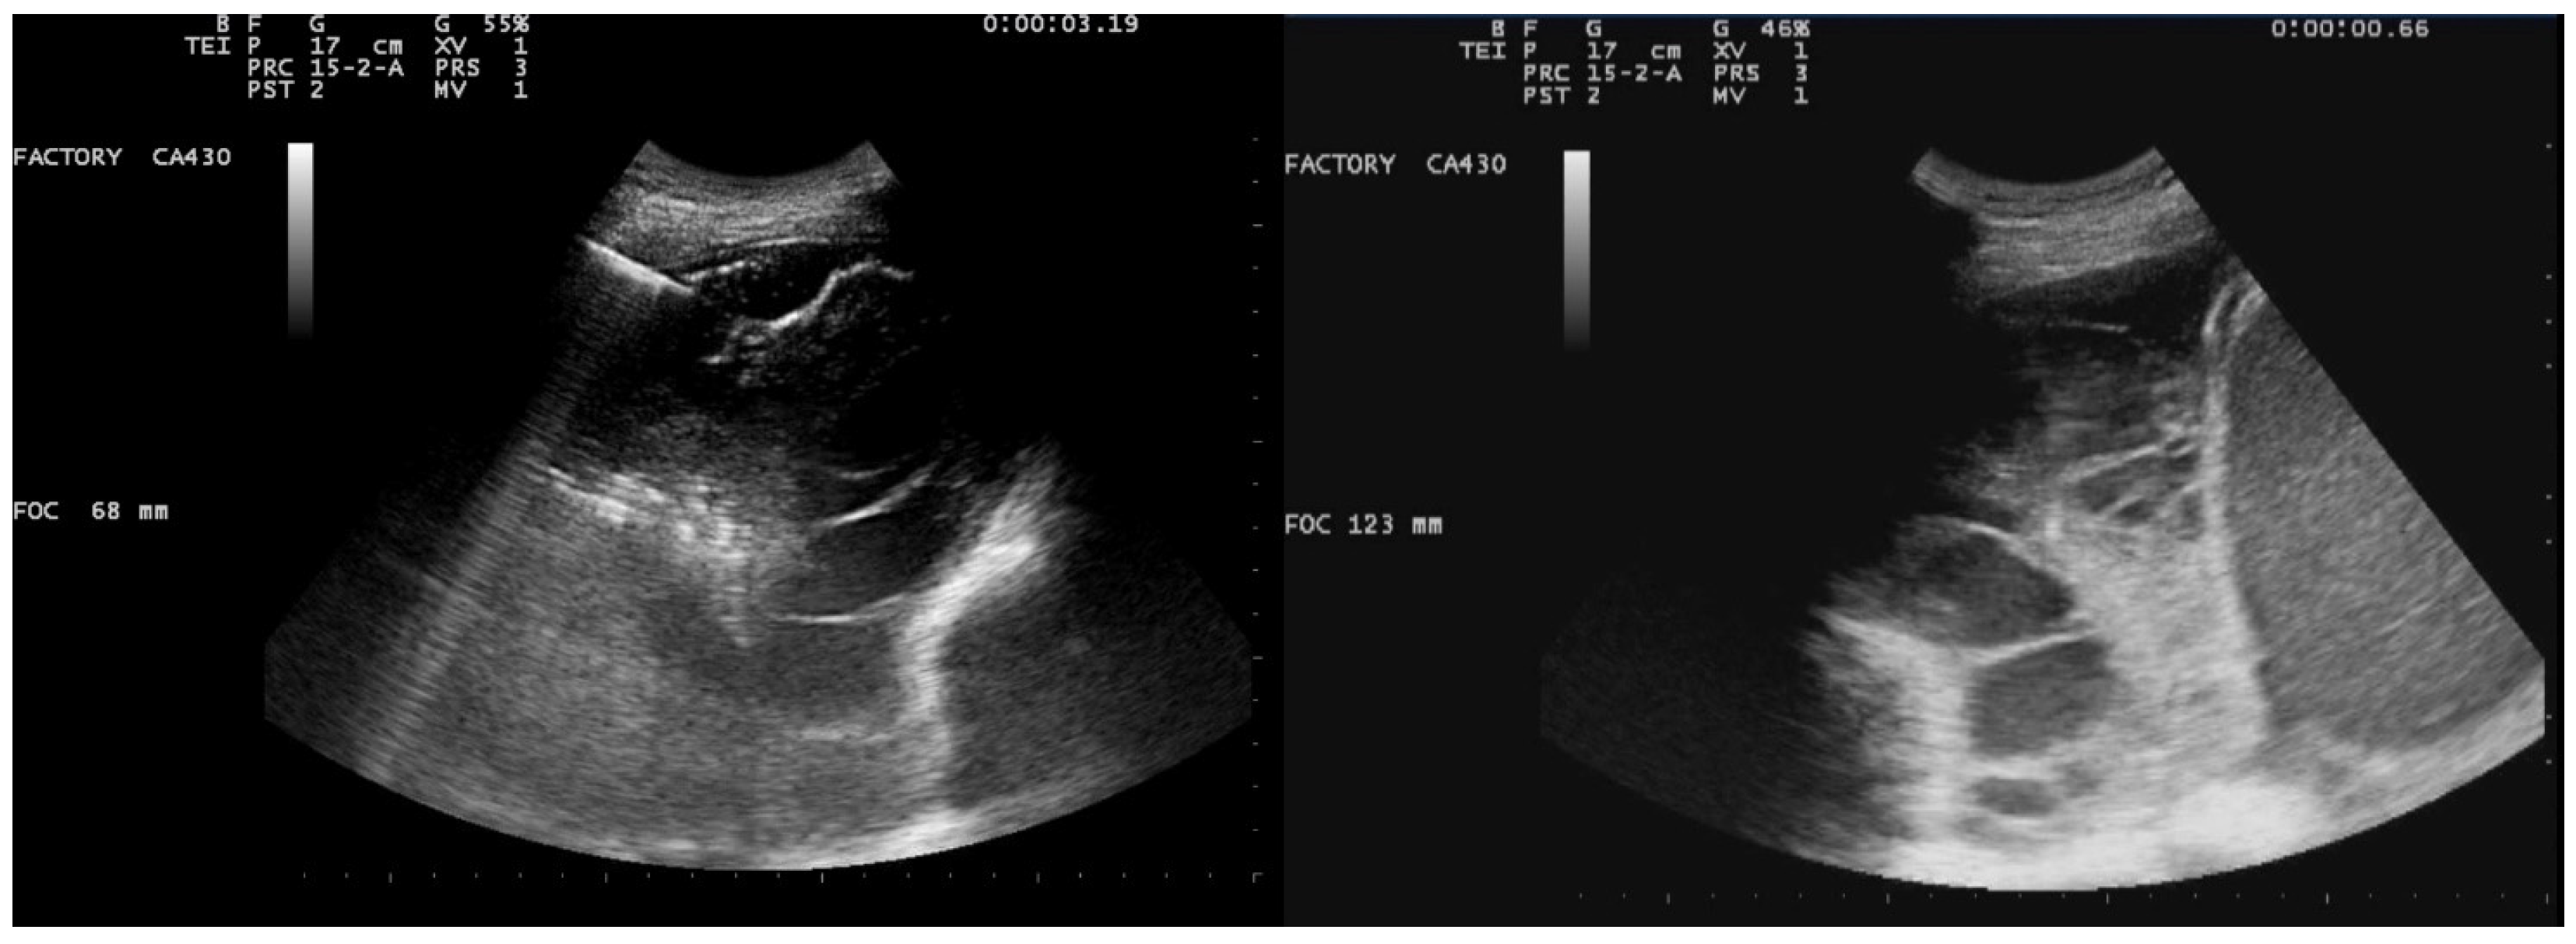

A 61-year-old female patient with obesity, discoid lupus, bipolar disorder, arterial hypertension, and hypothyroidism was admitted to our Respiratory Unit for respiratory failure and evidence of a large complex PEff on her chest CT, which also revealed complete atelectasis of the right lower lobe (RLL) and almost-complete atelectasis of the middle lobe (ML) and right upper lobe (RUL) (Figure 6). There was also a solid tissue surrounding the right main bronchus and its main branches, which was suspected to be neoplastic. It had a central hypodense area consistent with necrosis.

Peripheral enhancement of the pleural layers was also observed.

Figure 6. Chest CT scan of the mediastinal window in the coronal (A) and axial (B) plane, showing a large right pleural effusion, occupying almost the entire hemithorax with organized appearance. There is also a complete right lower lobe atelectasis and almost-complete right middle and upper lobe atelectasis with sparing of anterior sectors.